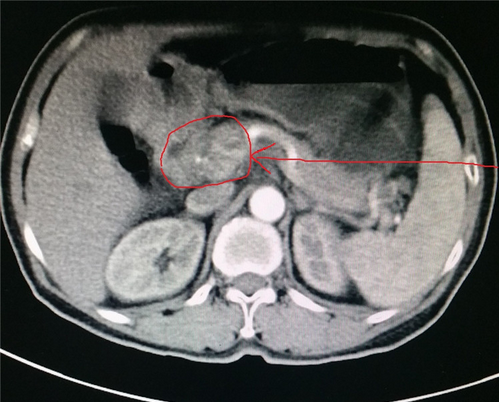

2017-07-07(治疗前)腹部强化CT:胃窦癌伴腹膜后、腹腔淋巴结转移,累及胰头,胰腺颈。

2017-09-03(治疗后)腹部MRI提示:腹腔内无淋巴结肿大。

患者2月前来的我院肿瘤科,考虑到患者年龄大,饮食少,伴有腹痛,体质差,预计生存期3月。我院肿瘤科杨金山副主任医师与中医专家田思强科主任进行中西医结合讨论,充分论证,对这种病情复杂的肿瘤晚期患者,决定采取单药口服化疗及中药调理。单药口服化疗具有副作用小的特点,结合中药扶正祛邪,调节免疫等干预。经2周期的精心治疗,2017-09-03查腹部MRI提示:腹腔内转移瘤消失,胃窦部肿瘤明显缩小。患者饮食、体力状况明显改善,腹痛缓解,能独立正常生活,患者及家属满意。中西医结合治疗凸显了在肿瘤治疗的优势。